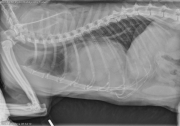

Today’s case is a 13-year-old male neutered domestic shorthair cat with intermittent chronic cough, presenting in respiratory distress. What are your differential diagnoses?

R LAT Thorax

There is marked enlargement of the cardiac silhouette. The cardiac silhouette silhouettes with the diaphragm, and there is a soft tissue opacity with apparent connection between the cardiac silhouette and diaphragm. There are multiple lobular soft tissue opacities and fat opacities superimposed on the cardiac silhouette on the lateral projections. There is a diffuse bronchointerstitial pattern throughout the lungs. The liver is not clearly visualized within the abdomen. The spleen and stomach are located more cranially than expected. There is gas lucency in the soft tissues dorsal to the thoracic spine likely secondary to subcutaneous injection.

The appearance of the cardiac silhouette is most consistent with a pericardial peritoneal diaphragmatic hernia. Ultrasonography could be considered to evaluate the organs displaced into the pericardial space.

The diffuse bronchointerstitial pattern is likely due to chronic lower airway disease. This may have infectious and noninfectious inflammatory components.

Both of these conditions can be contributing to the current clinical signs of dyspnea. Airway sampling is recommended to further evaluate the lower airway disease. Echocardiography could be performed to rule out cardiac disease.

PPDH and chronic lower airway disease.

The dyspnea improved with medical therapy for the chronic lower airway disease. Surgery to correct the PPDH was discussed however not performed at this time.